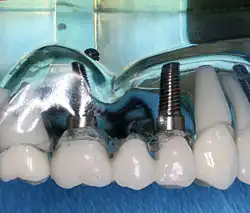

Im November 1895 entdeckte Wilhelm Conrad Röntgen die später nach ihm benannten Röntgenstrahlen, die die Untersuchung des Kiefers vereinfachten. Als Mittel zur örtlichen Betäubung von Zahnschmerzen wurde im Jahre 1905 das Lokalanästhetikum Procain von den deutschen Chemikern Alfred Einhorn und Emil Uhlfelder entwickelt, die dem Wirkstoff den Namen Novocain (lateinische Wortschöpfung für „Neues Cocain“) zuordneten. Damit waren die Grundlagen für eine moderne Diagnostik und Therapie gelegt. Die Zahnheilkunde erlebte daraufhin einen rasanten Fortschritt: von der Entwicklung zahlreicher oralchirurgischer Verfahren bis zur Anfertigung von Zahnersatz mittels CAD/CAM-Verfahren. Parallel zum Fortschritt der wissenschaftlichen Zahnheilkunde entwickelte sich das Berufsbild, was in der Geschichte des Zahnarztberufs dargestellt wird. Daneben entwickelte sich die Tierzahnheilkunde, die sich entsprechend modifizierter Verfahren der allgemeinen Zahnheilkunde bedient.